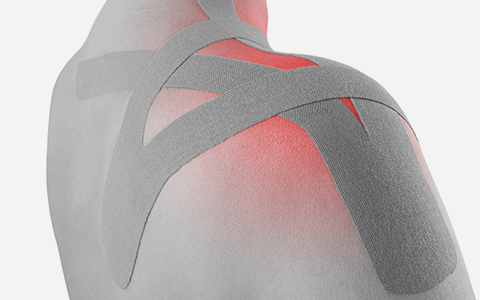

주사치료

주사치료

원인 신경 차단

원인 신경 차단

실시간 영상 확인

실시간 영상 확인

빠른 통증 감소

빠른 통증 감소

빠른 일상생활 복귀

빠른 일상생활 복귀